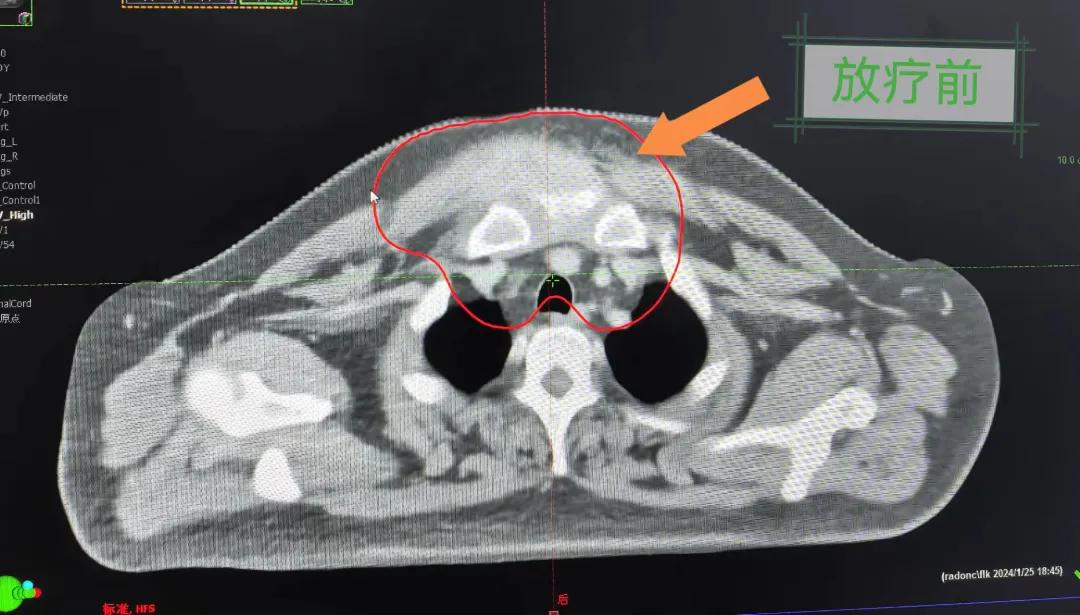

2個月前,市二院放療科接診了一名特殊的病人。一位40歲的中年男人,其前胸部竟然長了一個巨大的大腫塊,已有8cm左右且疼痛。

經(jīng)過詳細詢問病史,得知患者半年前前胸部突然出現(xiàn)一個腫塊,最初并未引起重視,以為只是普通囊腫,就隨便抹點藥,貼了膏藥。然而,腫塊并未縮小,反而逐漸增大,并伴隨著難以忍受的疼痛,嚴重影響了患者的日常生活和工作。隨后就診于當?shù)蒯t(yī)院,行“胸部腫物穿刺活檢術”,術后病理提示為鱗狀細胞癌。突如其來的打擊讓患者不知所措,盡管嘗試了保守治療,但效果并不理想,僅能暫時緩解疼痛。

患者經(jīng)多方咨詢與打聽,在家屬的陪同下來到市二院放療科找到趙亮主任尋求幫助。入院后迅速完善了相關檢查,診斷為罕見的“胸壁腫瘤”。因腫瘤體積大,侵犯周圍組織,手術治療難度較大,經(jīng)院內多學科會診后,決定采用無創(chuàng)的局部放射治療。在初步告知患者及家屬治療方案時,病人及家屬都擔心預后及放療可能引起的不適,趙亮主任詳細且耐心的向家屬和病人講述放療過程中可能出現(xiàn)的不良反應,確保讓他們安心治療。

隨后,趙亮主任帶領放療團隊以最快的速度完成了患者的放射治療計劃,在保證放療精準打擊腫瘤的同時,利用先進的三維立體精確放療技術,最大限度的避免心臟、肺部的損傷發(fā)生,整體治療精準度達到1mm以內。經(jīng)過10次的放射治療后,患者疼痛已明顯減輕,胸部腫物肉眼可見的縮小,患者及家屬臉上終于露出久違的笑臉。